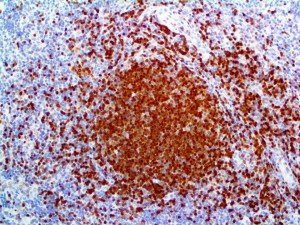

It is the ICU physician who is most likely to witness one of the deadliest manifestations of the abnormal immunological response, the cytokine storm syndrome (CSS). This response is also referred to by some as the cytokine release syndrome (CRS). CSS is characterized by continuous activation and expansion of macrophage and lymphocyte populations, which secrete large amounts of cytokines, causing the cytokine storm. This massive cytokine release is akin to hemophagocytic lymphohistiocytosis (HLH) disease, a syndrome characterized by initial unchecked and persistent activation of cytotoxic T lymphocytes and NK cells.

Clinical and laboratory manifestations of HLH include fever, enlarged liver and/or spleen, neurologic dysfunction, coagulopathy, liver dysfunction, cytopenias (i.e., low levels of erythrocytes, leukocytes, and/or platelets), hypertriglyceridemia, hyperferritinemia, hemophagocytosis, and eventually diminished NK cell activity as the immune system becomes progressively paralyzed. HLH can be familial (primary HLH) or secondary to another disease process (sHLH), such as rheumatic disease, in which it is referred to as macrophage activation syndrome (MAS, characterized by elevated ferritin).